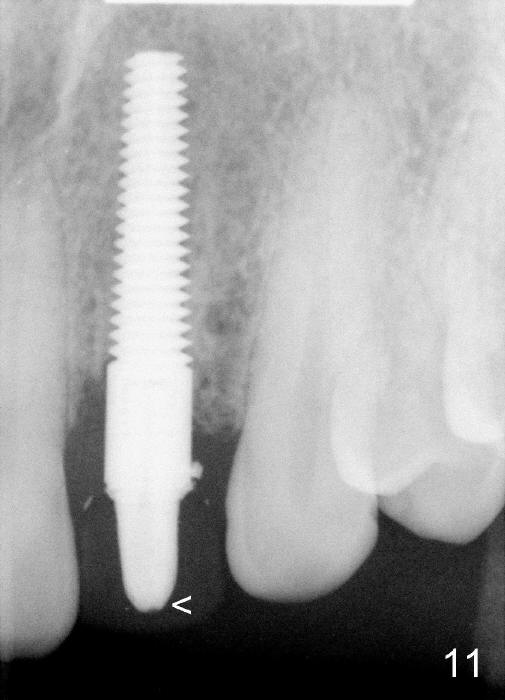

A 49-year-old lady has failed endo on the upper left lateral incisor (Fig.1,2). A gutta percha inserted to the buccal fistula (Fig.1 >) shows a mesial defect (Fig.2<). There is a large buccal apical defect, corresponding to the lesion shown in Fig.2 *, when the affected tooth is extracted. After thorough debridement and Clindamycin soaking, osteotomy is initiated in the palatal wall of the socket. Demineralized freeze dry cancellous bone graft is placed in the buccal defect. A 4x20 mm gingiva-level tapered implant is placed with insertion torque 50 Ncm (Fig.3). A 3x5 mm 20 ° offset abutment is inserted and cemented (Fig.4,5). A retentive groove is prepared on the abutment and the underlying implant; chamfer margin placed on the implant (Fig.4,5). A provisional is fabricated and cemented temporarily (Fig.6,7). Excess cement is removed, followed by removal of gingival retraction cord. There is no contact in centric and non-centric occlusion.

The gingival architecture around the immediate provisional is normal 5 months postop (Fig.10,12). To increase cosmetics for the definitive restoration, the abutment length is reduced (compare arrowheads in Fig.11 to 12).